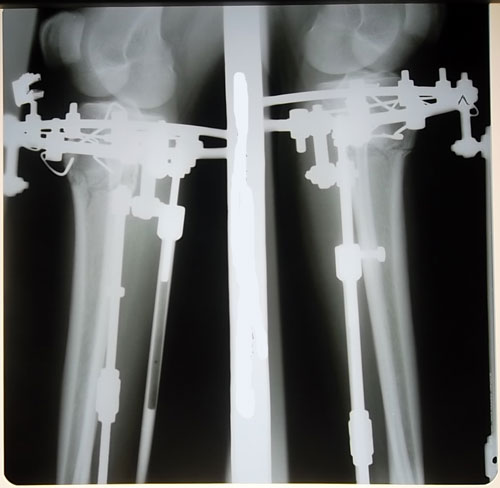

Всем привет.конешно я поздно начинаю свои дневник так получилось.сегодня 23 дня после ОП.я так рада что приехала и зделала ОП.очень долга собиралось у знала про клинику давно когда еще реклама была в газете ВРЕМЯ.я очень рада что приехала и зделала ОП даже и невериться что я вздесь нахожусь.ОП зделали 28 июля конешно боялась перед операци плакала и так после наркоза плакала от наркоза отошла быстро.на второй день после ОП еле лел стала так было больно но неходила думала что я долга несмогу стать но нет на трети день стала и начала ходит сходила в туалет и помылась и в тот день сама помыла голову всему этому была рада.с не терпением ждала круток и боялось что будет больно.но вовремя круток мне небыло больно.все эти дни у меня небыло сильных боли.и сама себе говорила что у меня все будет хорошо и все проидет хорошо. себя настраивала только на хорошое.когда приехала в клинику вздесь было 7 девчонок которым уже зделали ОП.в тот день когда я приехала приехали еще двое.со всеми познокомились поговорили.щас еще приехали двое сегодня делаеть одному ОП.за время провывание в клинике пятеро приежали на снимку аппарата ноги получилось красивые.даже незнаю че писать в начале после ОП так хотела много чего писать но у меня небыло пароль.завтра уежаю домой.ну наверно на этом все.

Ух ты! Ножки супер!